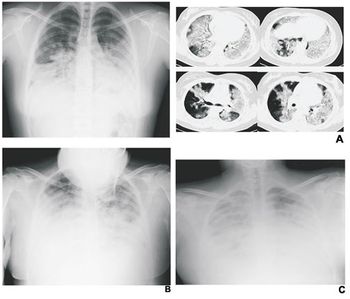

Cancer survivors and others with chronic conditions, backed by patient advocacy groups, gathered on Capitol Hill in Washington, DC, Wednesday to protest proposed imaging services reimbursement cuts they fear will reduce access to essential diagnostic imaging services, particularly in rural communities.